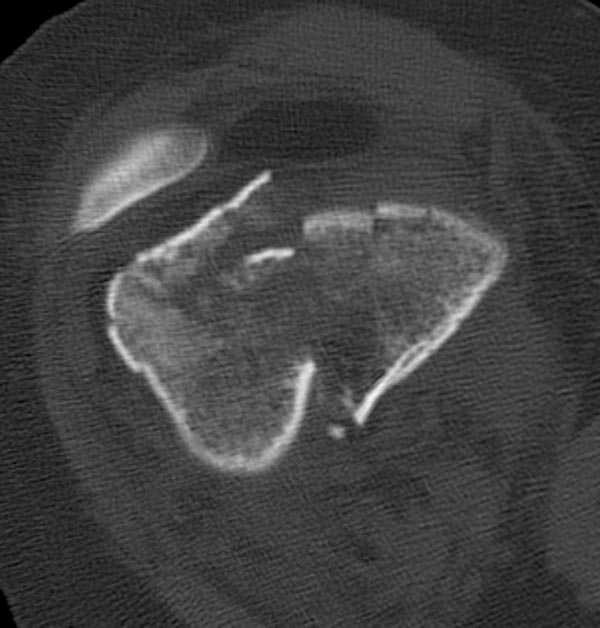

Это перелом не нижней трети, а дистального суставного конца, с распространением на диафиз. Что-то между C2 и C3. Но пока ближе к C2 по увиденному - вторую проекцию еще не показали.

На профиле стало видно, что открываться придется, это перелом C3, хотя можно назвать и C2+, т.е. с еще и фронтальным раскалыванием одного мыщелка. Надо сделать медиальную артротомию, ступеньку на внутреннем мыщелке устранить, ввести либо несколько временных спиц спереди назад, или сразу винт вдоль эллипса мыщелка. А дальше как выше написано - дистрактор, и штифтовать. Учитывая наличие открытого колена - вполне уместно ретроградно.